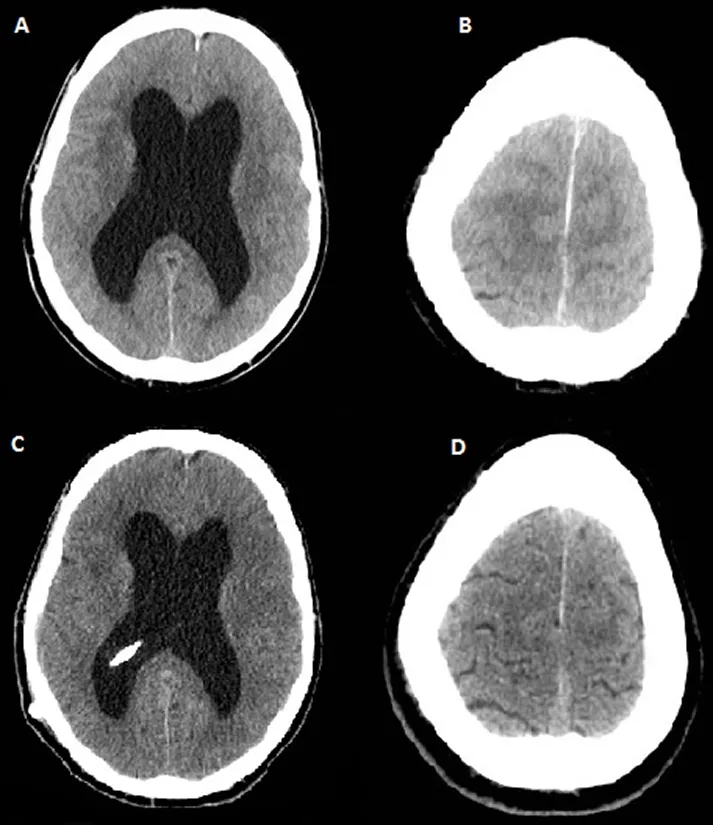

Understanding hydrocephalus in adults